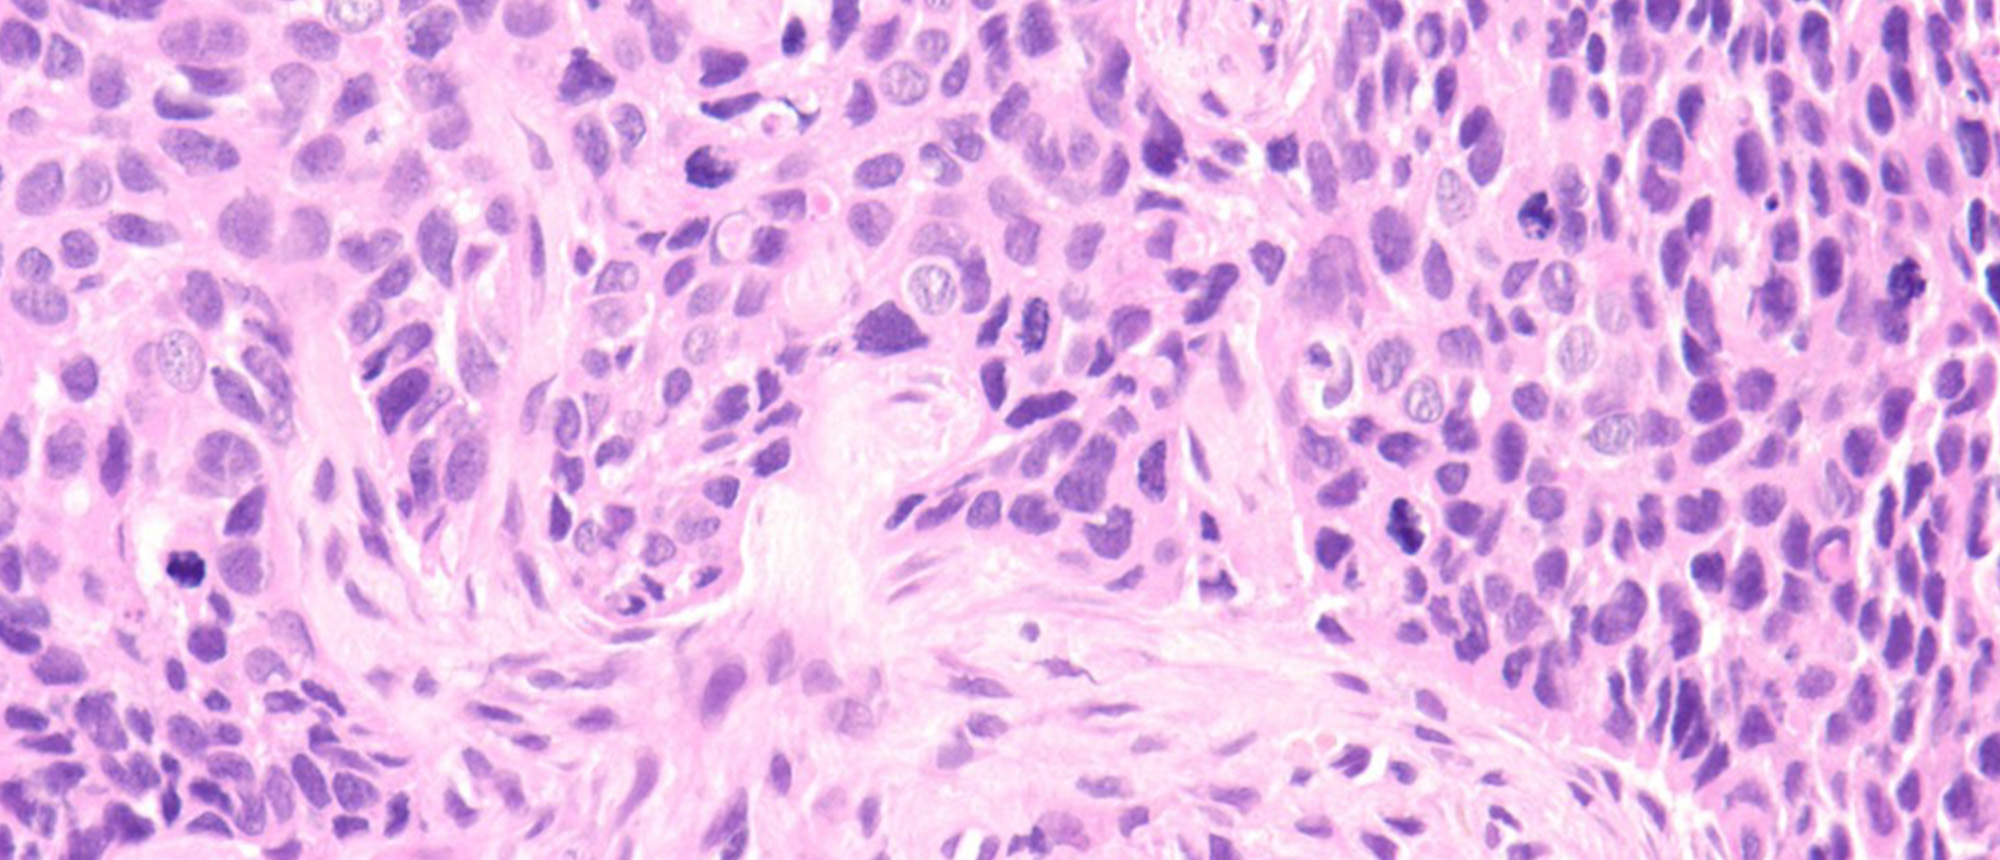

Orbital Necrotizing Fasciitis

Specialty: Ophthalmic Pathology

Type: Online Grand Rounds

Include in Catalogue?: Yes

Presenter(s): Sugi Panneerselvam, MD

Faculty Discussant(s): Sander R. Dubovy, MD; David T. Tse, MD

Presenter/Faculty: Dubovy, Panneerselvam, Tse

Orbital Necrotizing Fasciitis A patient found down by EMS with left orbital swelling for 2 days after he was unable to take his medications due to a recent illness. He was admitted to a hospital and treated for diabetic ketoacidosis, Group A Streptococcus sepsis and left orbital infection before pr…